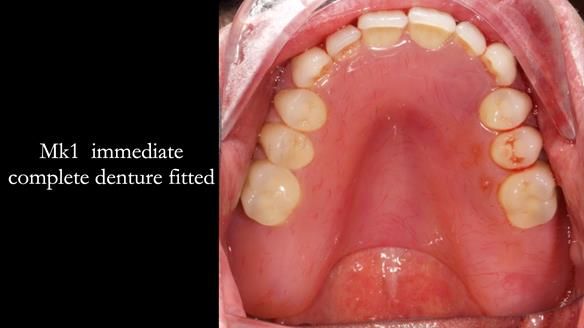

- Retain the upper canines (13 and 23) after root canal treatment, to support a Mk1 immediate complete denture.

After fitting the Mk1 immediate denture, Jeremy experienced speech problems, particularly with ‘s’ sounds, and felt the denture was too bulky, restricting his tongue. Although the appearance was good, the speech issues could not be resolved.